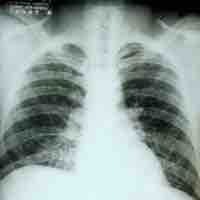

Tuberculosis is a common, and in many cases lethal, infectious bacterial disease that mainly affects the lungs.

Pneumonia is an inflammatory lung disease that can lead to problems with breathing, often caused by bacterial infections.

Pneumocystis pneumonia (PCP) or pneumocystosis is a form of pneumonia, caused by the yeast-like fungus Pneumocystis jirovecii.